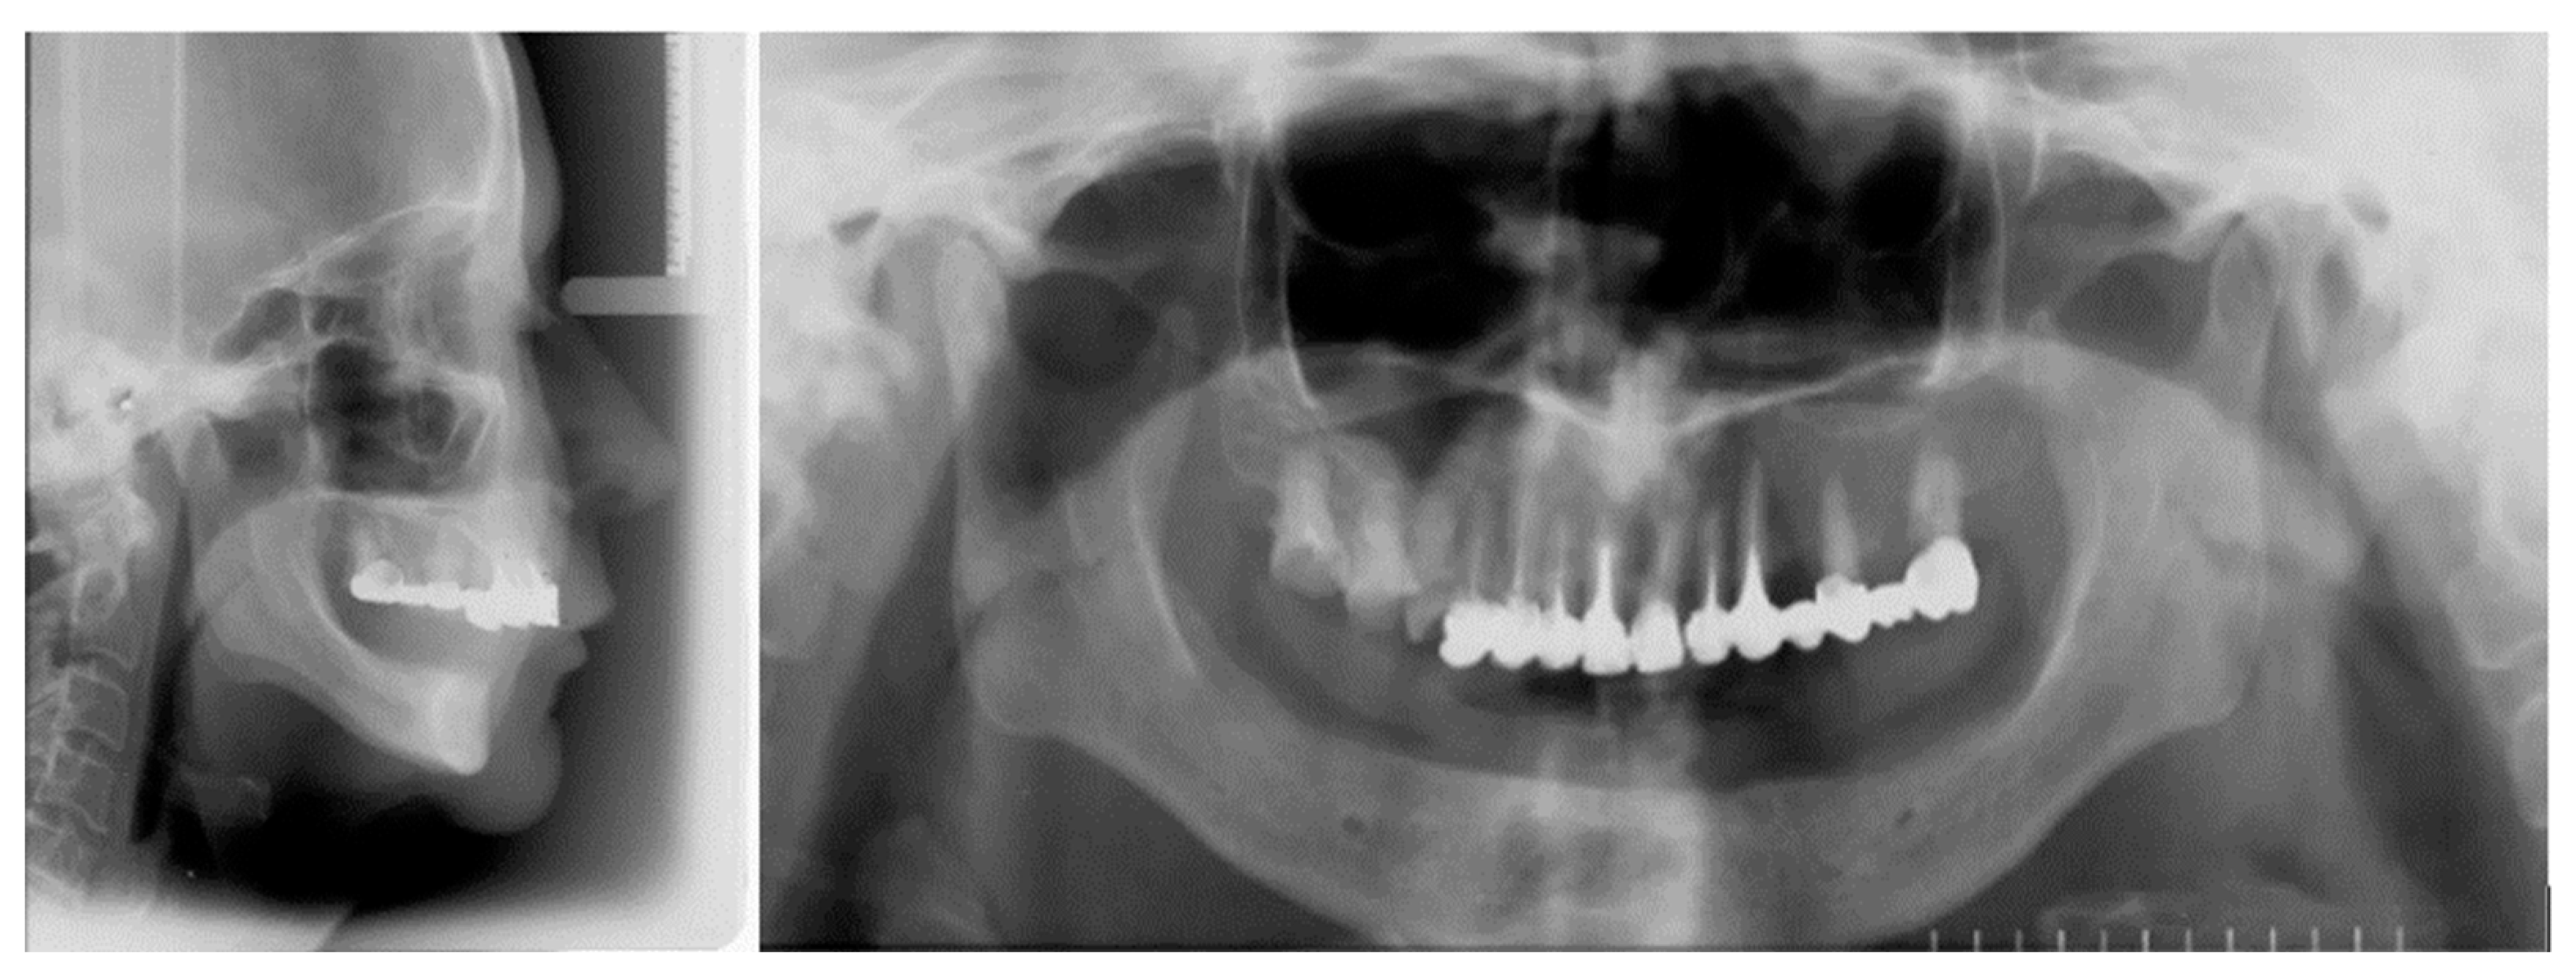

2.2. The Implant-Prosthetic Treatment Plan